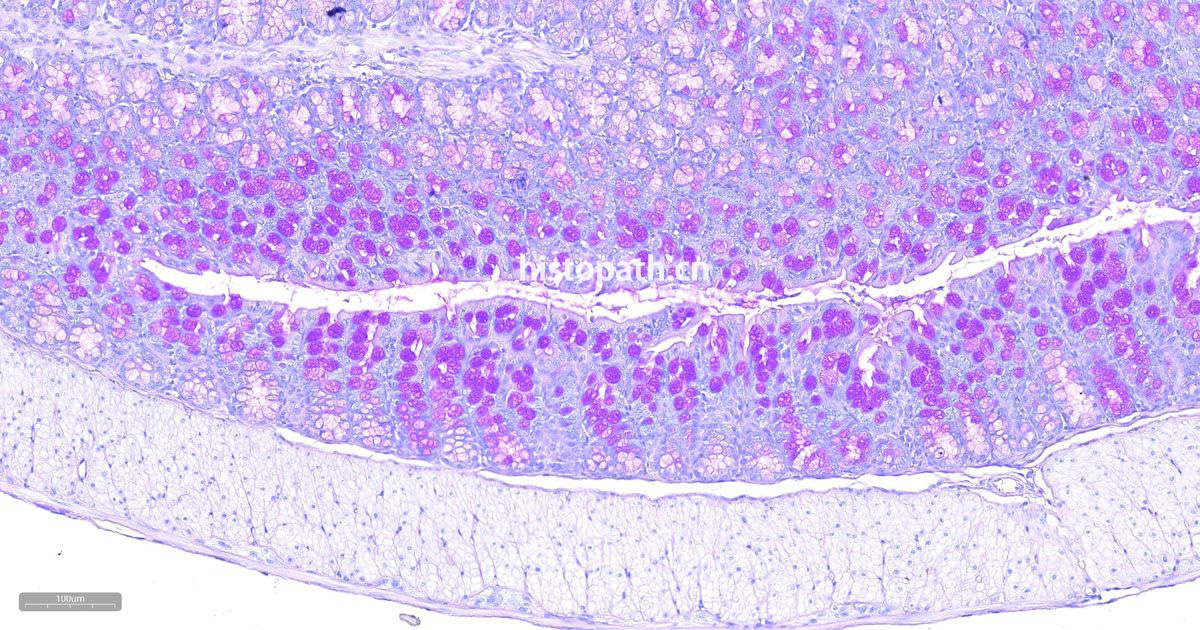

PAS染色,又称为过碘酸-雪夫染色,因其主要用于多糖(polysaccharides)如糖原(glycogen)和粘性物质(mucosubstances)如黏多糖(glycosaminoglycan)、黏蛋白(mucins)、糖蛋白(g lycoproteins)和糖脂(glycolipids)等物质的染色,所以也称糖原染色(Glycogen Staining)。过碘酸-雪夫染色是病理学中常规的染色方法之一,McManus在1946年最先使用过碘酸-雪夫技术显示黏蛋白,该染色法不仅能够显示糖原还能显示中性粘液性物质和某些酸性物质以及软骨、垂体、真菌、色素、淀粉样物质、基底膜等。另外,临床诊疗中PAS染色常用于辅助淋巴细胞性白血病的诊断。

糖原是由D-葡萄糖的分支或直链组成的高分子多糖类化合物,糖原的合成与分解代谢主要发生在肝、肾和肌肉组织中。过碘酸是一种强氧化剂,能将组织或者细胞中的糖原及有关物质中的1,2-乙二醇基(CHOH-CHOH)氧化成两个游离醛基(- CHO),且过碘酸的特点是不再继续将醛基氧化成羧基。Schiff试剂(Schiff reagent),又称品红亚硫酸试剂,含碱性品红和亚硫酸,碱性品红与亚硫酸结合后,失去醌式结构而生成无色品红。无色品红与过碘酸氧化的游离醛基结合,醌式结构恢复,生成洋红色(magenta)产物,定位于胞浆,颜色没深浅与多糖含量成正比。

染色结果分析:糖原、多糖类物质及其他PAS反应阳性物质呈洋红色,细胞核呈蓝色。